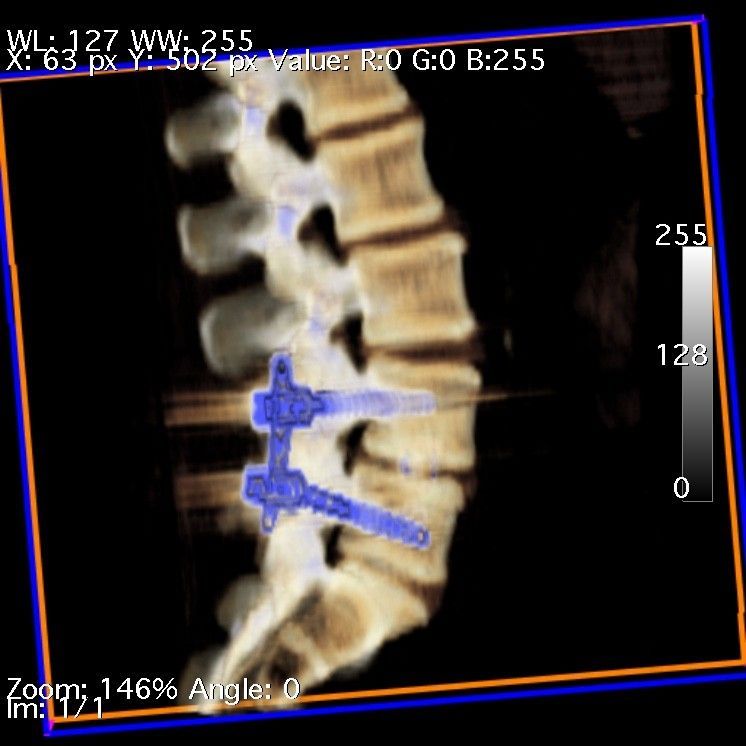

Patologia Degenerativa da Coluna Vertebral

- Tratamento de doenças que afetam a estrutura e função da coluna, com potencial impacto na qualidade de vida.